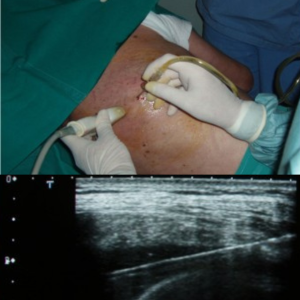

Ultrasound-Guided Pleural Tapping

A safe, minimally invasive procedure to remove excess fluid from the pleural space using ultrasound guidance, aiding in diagnosis and relieving respiratory discomfort.

Percutaneous Drainage